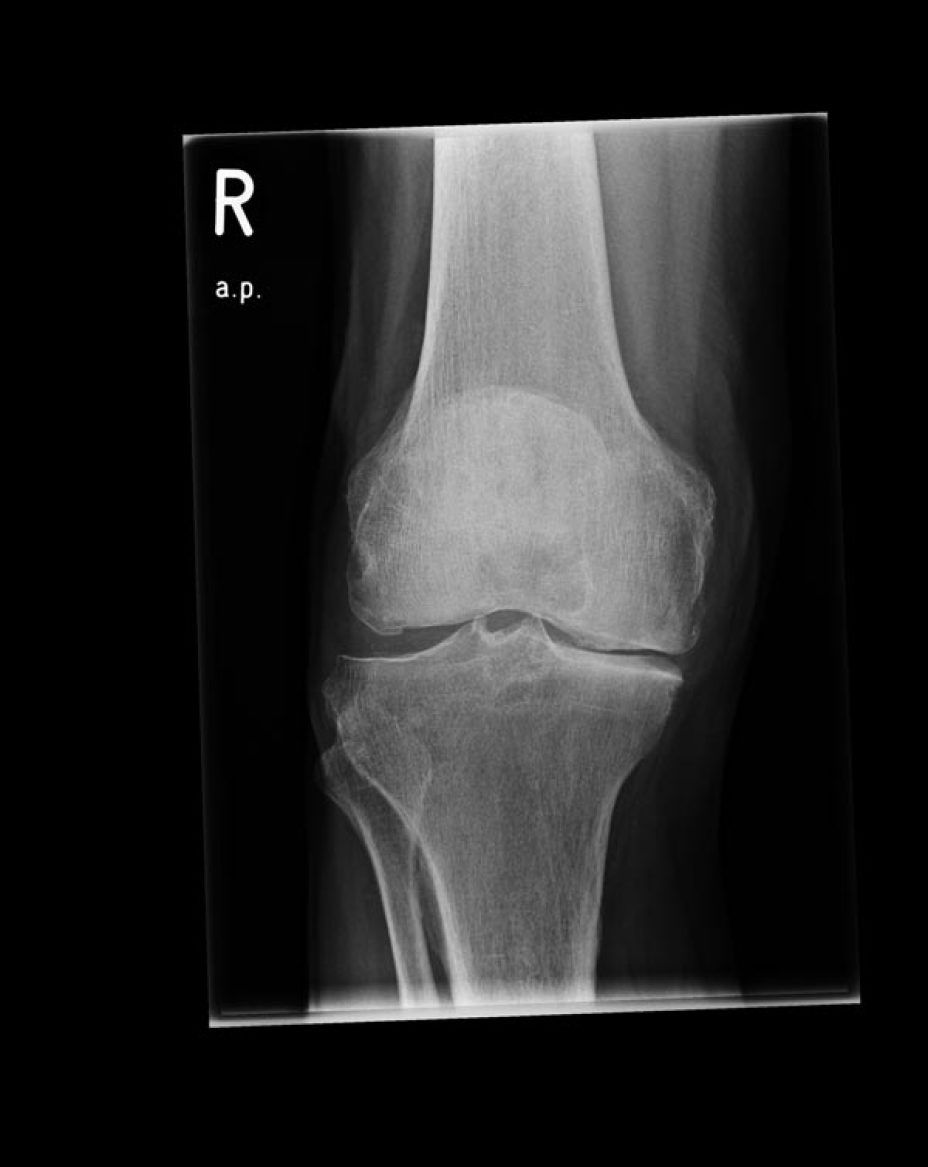

- Coxarthrose, Gonarthrose, Omartrhose sowei Polyarthrose (Gelenkverschleiß)

- 64% der Patienten mit Kniearthrose